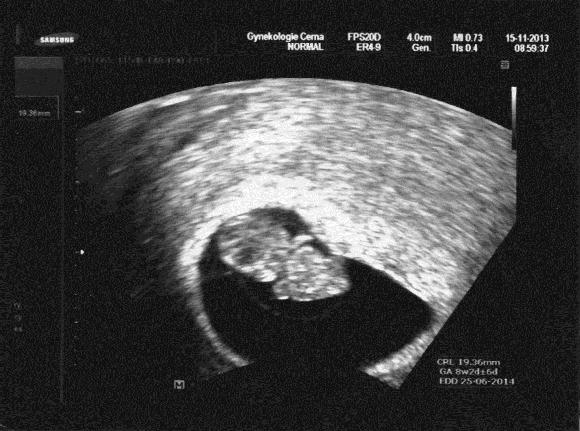

Ahojík holky... tak já v pátek po kontrole, naštěstí vše v pořádku ,dnes jsem 8+3 a na fotečce s UTZ je krásně vidět hlavička,ručičky a manžel tam prej vidí pindíka,hihi

[390788] Krásná fotečka :-) Já tam vidím tu hlavičku a ručičky - zbytek je na fantazii

My jsme dnes 8+1 a měli jsme v 7+5 14mm